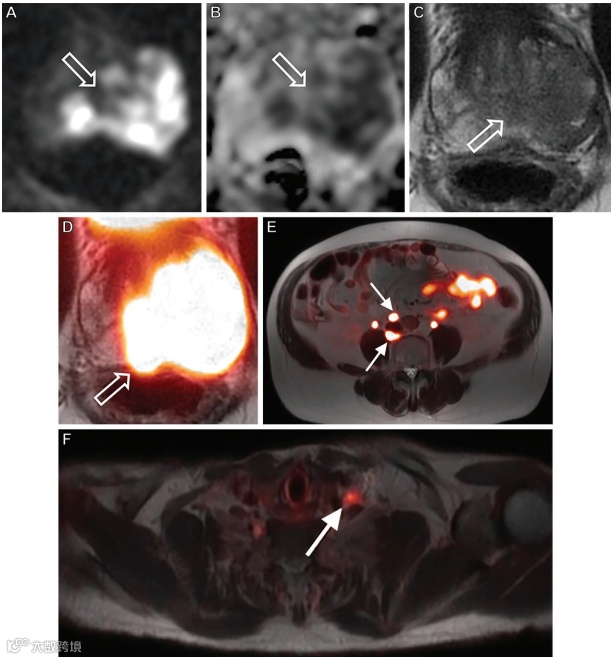

图3. 一位65岁的男性患者,新近被诊断出Gleason 4+4级前列腺癌,应用68Ga-PSMA-11 PET/MRI对其进行初始分期。

轴位高b值扩散加权成像(A)、表观扩散系数成像(B)、T2加权(C)、融合PET/MR(D)图像显示一个大的前列腺内肿瘤(箭头)占据腺体左侧的大部分。(E,F)额外的轴位融合PET/MRI图像显示在腹膜后和左锁骨上窝有大量亚厘米淋巴结转移(箭头)。